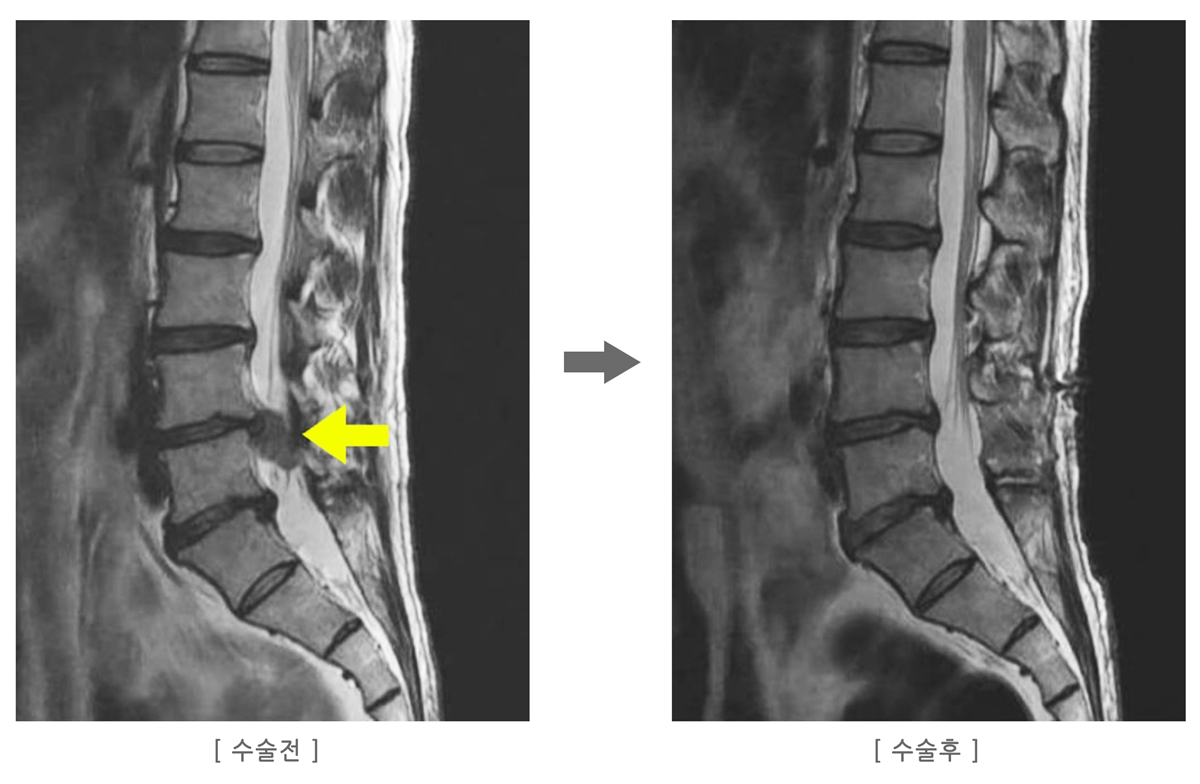

‘허리디스크 재발’은 수술을 통해 제거된 디스크 부위가 다시 파열되거나, 새로운 부위에서 디스크가 튀어나오는 현상을 말합니다.

하지만 디스크는 수술 이후에도 3~6개월 동안 ‘봉합되지 않은 열린 상태’로 남아 있어 자세 관리가 매우 중요합니다.

- 수술 후 디스크 터진 척추사이의 구멍과 디스크를 빼낸 공간은 그대로 비어있게 되어 디스크가 조금씩 빠져나오게 됩니다.

- 디스크는 액체가 아니라 젤과 같은 반고체 상태이기 때문에 척추사이에 구멍이 있더라도 잘 빠져 나오진 않습니다.

- 척추사이의 구멍이 막히고 빼낸 공간이 채워지는데 수술 후 약 6개월의 기간이 필요하게 됩니다.

- 이 시기에 허리를 C자로 유지하지 못하고 잘못된 자세, 무리한 움직임, 앉아있는 자세 등이 잘못되면 그 구멍을 통해 디스크가 더 많이 빠져 나와 통증이 다시 시작됩니다.

저는 6개월 동안 디스크가 계속 빠져 나온다는 사실을 몰랐습니다. 수술 후 통증이 줄어든 걸 보고 “이제 괜찮겠지”라는 안일함이 생겼고, 결국 사소한 움직임 하나로 디스크가 다시 터져 재수술을 받았습니다.